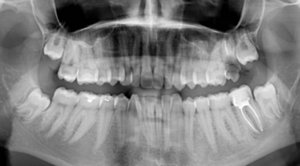

На протяжении трёх дней беспокоила несильная ноющая боль с правой стороны внизу. Сделали снимок, врач предположил, что боль возникает из-за зуба мудрости, который ещё не прорезался. И сразу записала на удаление.

Не знаю, можно ли что-то понять по приложенному снимку, но сколько примерно занимает удаление такого зуба и обязательно ли это?

Однозначно, причина беспокойств — это неправильно расположенная восьмёрка. Удаление необходимо, в противном случае мы получим скученность всего зубного ряда и потеряем седьмой зуб. Удаление сложное и требует профессионализма и опыта. Потребуется моя помощь — запишитесь к нам на приём к челюстно-лицевому хирургу.